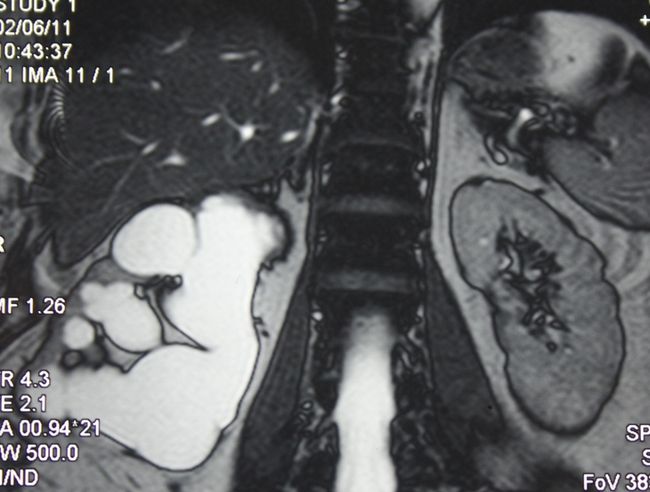

Гидронефроз III. Лапароскопическая нефрэктомия справа

Лапароскопическая нефрэктомия